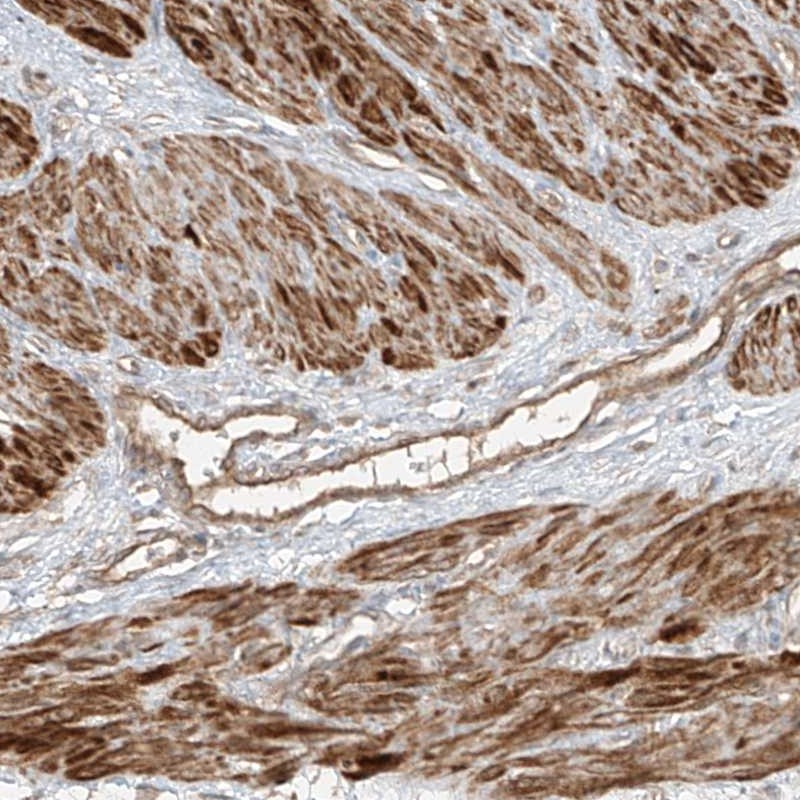

Immunohistochemical staining shows positivity in smooth muscle and endothelial cells.